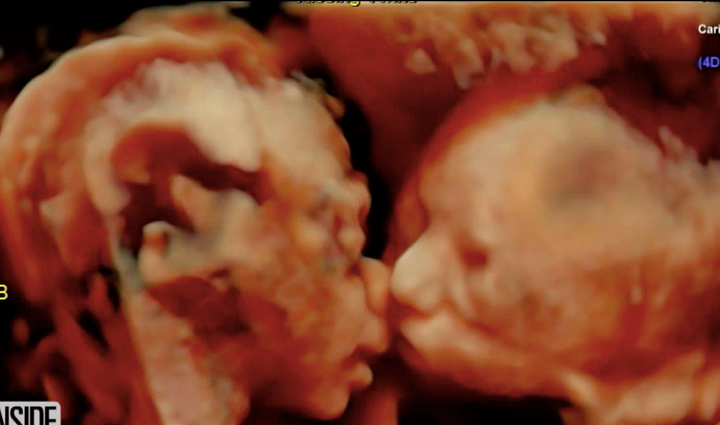

The sonogram showed something amazing: The two babies seemed to be kissing each other.

The ultrasound video shows “Baby B” appearing to kiss “Baby A” on the cheek.

“I’ve done 15,000 of these, and I’ve never seen twins face-to-face, looking like they’re kissing,” he told The Huffington Post. “Usually, one’s head is up and the other is down.”